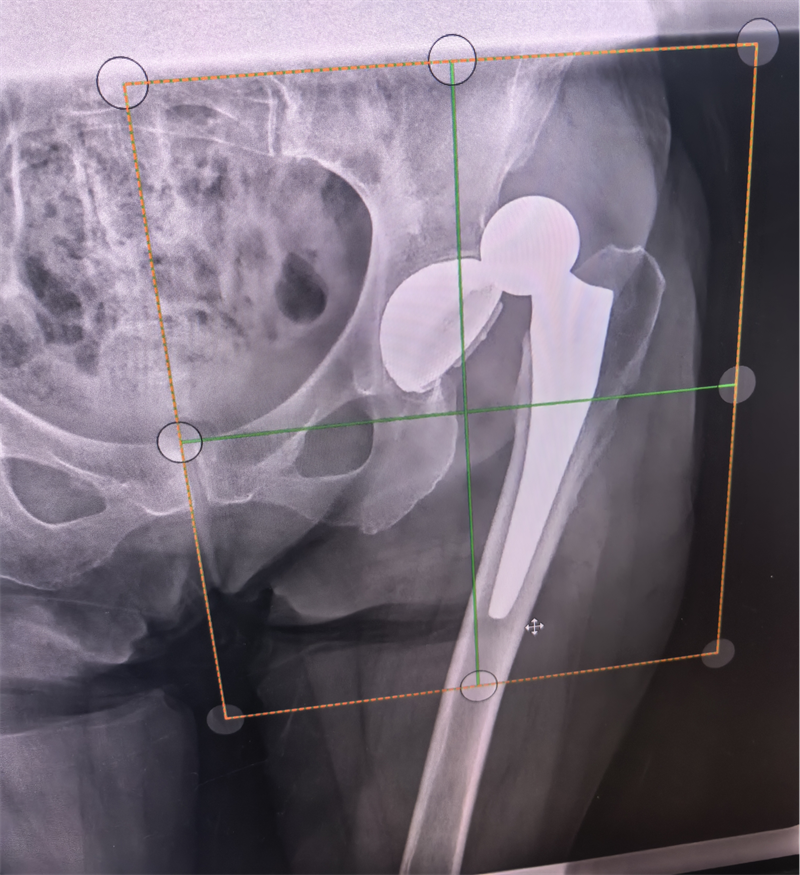

在门诊治疗室,樊磊以沉稳的手法,引导患者处于特定体位,运用专业技巧进行牵引、旋转与角度微调。整个过程,他不断与患者沟通,缓解其紧张情绪,并以精准的力度控制,稳健而轻柔地操作。短短数分钟内,随着一声轻微的“咔嗒”声,复位成功完成。影像学确认显示,关节已恢复至正常对合关系。

(患者拍片结果)